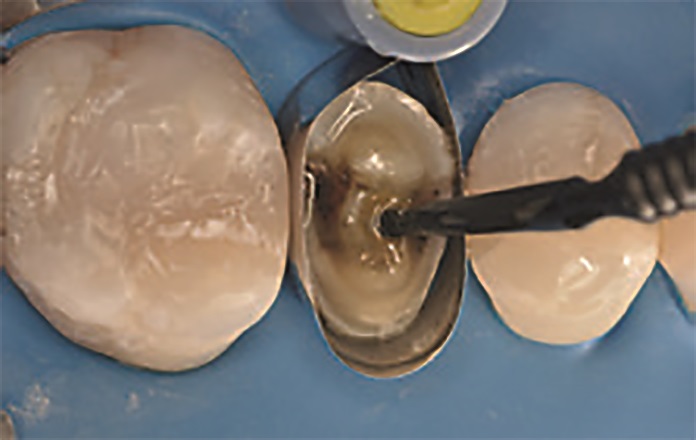

W przypadku odbudowy zęba 15 procedurę adhezyjną przeprowadzono z zastosowaniem protokołu wytrawiania self‑etch. Po dopasowaniu formówki Adapt SuperCap Matrix zaaplikowano OptiBond Universal zgodnie z wyżej opisanym protokołem — bez wcześniejszego zastosowania kwasu ortofosforowego (ryc. 12). Odstąpiono od użycia wkładów koronowo‑korzeniowych w tym przypadku. Wykonany dostęp endodontyczny umożliwił uzyskanie optymalnej retencji, a dzięki kształtowi zachowanych tkanek i długości korony zęba 15 osiągnięto rozległy efekt obręczy. Odbudowa została wykonana przy użyciu systemu SonicFill™2 – kompozytu bulk‑fill z końcówką dźwiękową do aktywacji materiału. SonicFill to kompozyt o wysokiej zawartości cząstek wypełniacza, zawierający opatentowaną żywicę ze specjalnymi modyfikatorami, reagującymi na energię dźwiękową. Na skutek aplikacji energii dźwiękowej i działania modyfikatora dochodzi do spadku lepkości i zwiększenia płynność materiału. Umożliwia to optymalne umieszczenie i dopasowanie wypełnienia do ścian ubytku. Po zaprzestaniu działania energii dźwiękowej kompozyt ponownie staje się bardziej lepki i zwarty, co sprzyja efektywnemu modelowaniu wypełnienia. Kompozyt ten cechuje się także optymalnym skurczem polimeryzacyjnym pozwalającym na wyższe stężenie inicjatorów sprzyjających bardziej efektywnemu procesowi polimeryzacji. Ponadto dzięki dopasowaniu współczynnika załamania światła i wydajnym mechanizmom utwardzania SonicFill2 jest możliwa jego polimeryzacja na maksymalnej głębokości wynoszącej 5mm. W związku z tym przed rozpoczęciem procedury zmierzono głębokość ubytku sondą, aby upewnić się, że grubość planowanej warstwy kompozytu będzie odpowiadała maksymalnej głębokości polimeryzacji tego materiału. Następnie wykonano odbudowę ubytku za pomocą jednej warstwy SonicFill2 (ryc. 13), który został spolimeryzowany za pomocą lampy Demi Ultra Light (ryc. 14). Po zakończeniu polimeryzacji usunięto formówkę, a wypełnienia w zębach 16 i 14 wykończono i wypolerowano za pomocą kolejnych krążków OptiDisc™ o coraz drobniejszym nasypie, a następnie jednoetapowego systemu Opti‑1Step™ (Kerr). Wygładzanie i polerowanie odgrywa istotną rolę w sposobie interakcji światła z uzupełnieniem. Mały, jednolity rozmiar cząsteczek materiału nanohybrydowego Harmonize™ został zaprojektowany w celu uzyskania optymalnej polerowalności.